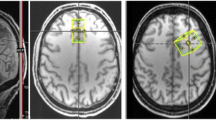

Two-dimensional multivoxel 1H-MRS was applied in two different orientations to estimate metabolites concentration using a PRESS (Point RESolved Spectroscopy) sequence [TR = 1700 ms, TE = 135 ms, FA = 90°, 3 averages, 1024 points, FOV = 160 × 160 mm, VOI (volume-of-interest) = 80 × 80 × 15 mm, thickness = 15 mm]. A 12 × 12 matrix yielded a 13.3 × 13.3 × 15 mm nominal voxel size. This matrix was interpolated to 16 × 16 leading to a voxel nominal spatial resolution of 10.0 × 10.0 × 15 mm; 1.5 mL. Automatic shimming was applied to offset field inhomogeneities and achieve well-resolved peaks for the metabolites in study86 and chemical shift selective (CHESS) weak water suppression was executed at 50 Hz bandwidth. For the 1H-MRS slice prescription, the centre of the VOI was aligned with the brain midline. Specifically, for the insula, putamen, and thalamus, the slice was aligned to AC-PC in the sagittal view, and the bottom of the slice was aligned with the bottom of the corpus callosum. Next, in the coronal view, the structures of interest were centred on the 1H-MRS grid, aiming for symmetric and maximum voxel coverage for each structure in each hemisphere. For the hippocampus region, the 1H-MRS slab was aligned in the sagittal view along the longest axis of the hippocampus and then centred in the VOI for both hemispheres, ensuring symmetric and maximum coverage in each hemisphere. Outer-volume lipid suppression was achieved by applying saturation bands. The 2D-CSI acquisition followed a weighted phase encoding scheme with a Hamming filter. Each 2D 1H-MRS acquisition lasted around 3.7 min.

The 1H-MRS data were analysed with LCModel v. 6.3-1D (Stephen Provencher Inc., Oakville, Canada87), wherein we quantified metabolite levels in institutional units, without water-scaling or correcting for T1 and T2 water or metabolite relaxation times. LCModel uses an a priori model (basis set) of the expected peak shape and position as opposed to a simple peak based fitting (based on arbitrary model functions). The basis set used for fitting included alanine (Ala), creatine (Cr), phosphocreatine (PCr), glutamine (Gln), glutamate (Glu), glycerophosphocholine (GPC), phosphocholine (PCh), gluthatione (GSH), myo-inositol (mI), lactate (Lac), N-acetyl-aspartate (NAA), N-acetyl-aspartyl-glutamate (NAAG), scyllo-Inositol (Scyllo), and taurine (Tau). Some metabolite peaks were considered as pools of compounds: total choline (tCho), total n-acetyl-aspartate (tNAA) and Glx, as the sum of GPC + PCh, NAA + NAAG, and Glu + Gln, respectively. Ratios to total choline and total creatine (tCr, the pool of Cr + PCr) were computed. Please note that the analysis of ratios to total choline is secondary and serves as a test for replication, because Cho concentration frequently varies in psychiatric diseases. For each region, the mean of both hemispheres was considered. Complementary analyses between hemispheres are reported in Supplementary Table S4. Two researchers (A.D. and A.E.) selected one voxel per brain structure for each participant and hemisphere, namely insula, hippocampus, putamen, and thalamus. Voxels were selected considering the coverage of the region-of-interest while being standardized as much as possible among participants, aiming at the same exact anatomical region. The coverage of the brain regions was evaluated by visual inspection with the BrainCSI software (Jeffrey Yager, University of Iowa Carver College of Medicine, Iowa City, IA USA, https://www.nitrc.org/projects/braincsi). In Fig. 4 we illustrate an example of voxel selection, for each region in study, as well as an example of LCModel output spectrum.